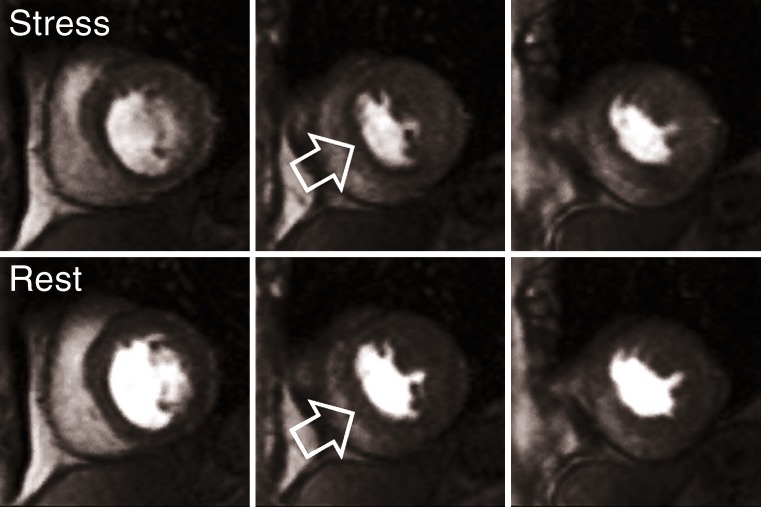

Fig. 7.

Combined stress (upper row) and rest (lower row) first-pass myocardial perfusion imaging (0.5 mmol/kg BW) demonstrating a reversible subendocardial perfusion deficit (arrows) in the inferioseptal and inferior aspect of the LV myocardium